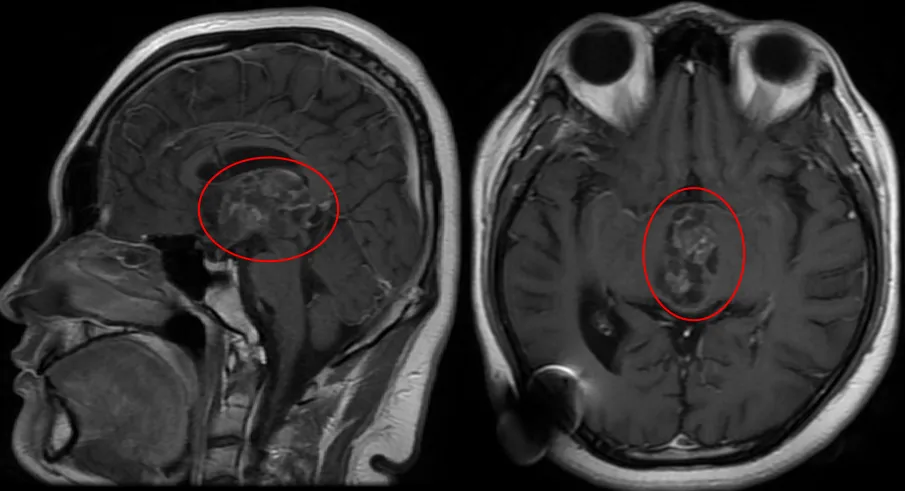

术前MRI

它在寂静中生长,直至危机再次浮现:飞宇的视力明显下降,出现视野缺损,看东西重影。MRI显示,一个40×25×31mm的巨大肿瘤已完全占据第三脑室,并从室间孔向下压迫中脑——这个少年的未来,正被阴影一点点吞噬。